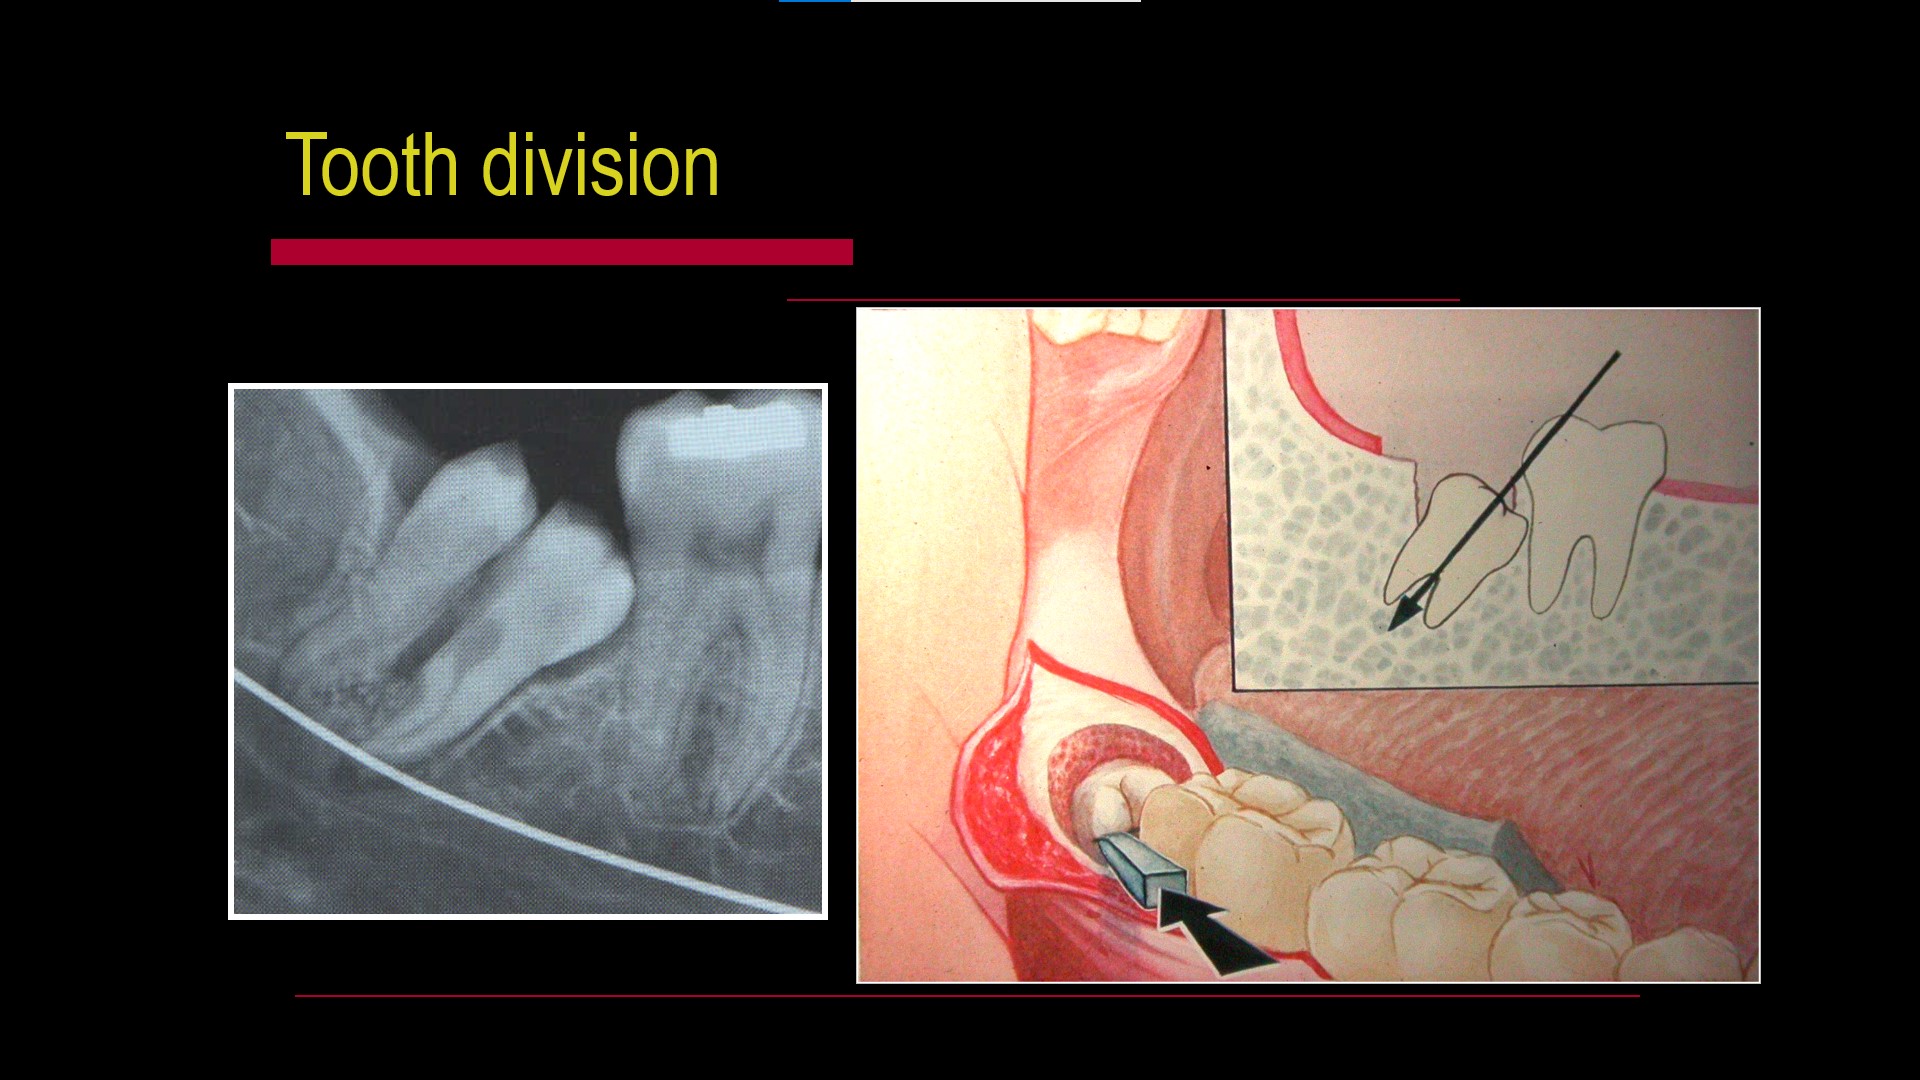

Impacted teeth